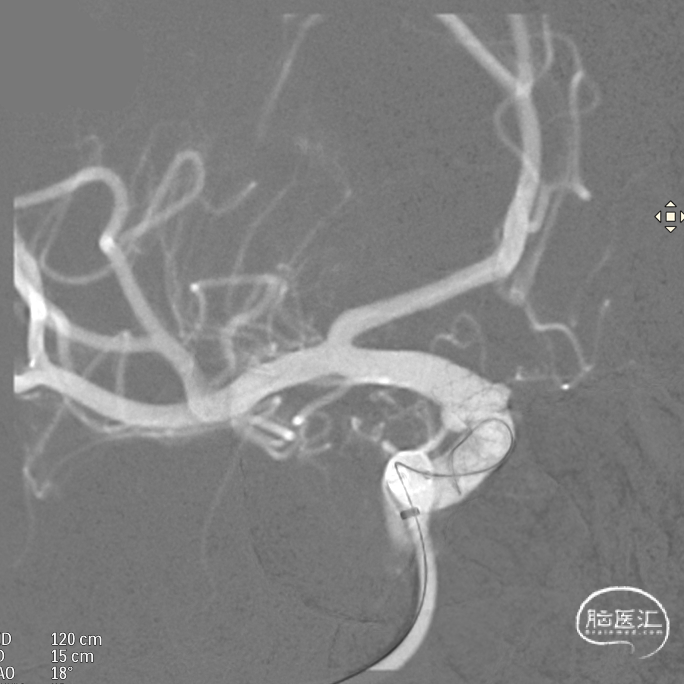

术后造影:支架覆盖两枚动脉瘤瘤颈,贴壁良好,瘤体内可见造影剂滞留。

术后支架显影: